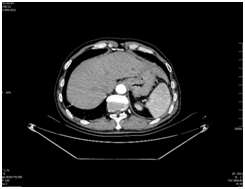

患者男性,58歲,合水縣農(nóng)民。術(shù)前胃鏡檢查、病理及胸腹增強(qiáng)CT檢查結(jié)果綜合提示,診斷為進(jìn)展期胃癌(cT3N2M0)。

(術(shù)前腹部增強(qiáng)CT顯示:胃底部胃壁增厚強(qiáng)化)